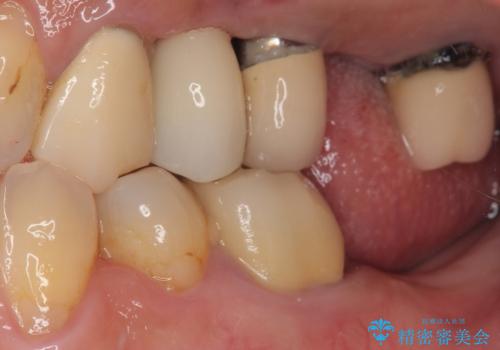

抜歯が必要な歯をインプラントに 短期間インプラント治療

- 抜歯が必要と言われ、インプラント治療を希望して来院された患者様です。

歯がボロボロで抜歯が必要な状態であり、後方にはインプラントが埋入されているため、同様にインプラントによる補綴治療を行うこととしました。

従来は4ヶ月ほど待機してからの埋入が一般的でしたが、歯肉の炎症が落ち着いた時点で速やかに埋入できるようになり、4ヶ月の短期間で治療を終えることができました。